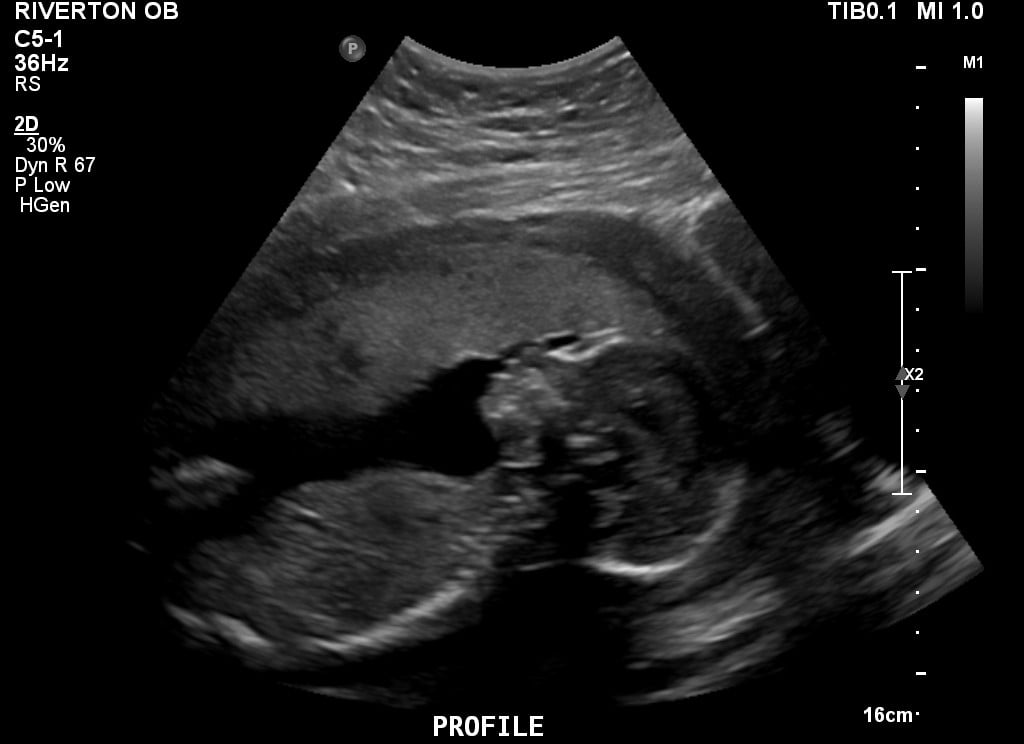

The doctor surprised me with an anatomy scan this morning! I'm 19w, scheduled to see a specialist next month for a fetal echocardiogram (just because we did IVF, and apparently that's standard.) This morning, regular OB was like "Eh, you're here and you haven't seen him in a while. Want to do the anatomy scan today?" I would have liked my husband to be there...but not enough to turn down an ultrasound!

Our little nerd stared down the "camera" the whole time. Would have loved one of those adorable profile shots...instead, he looks a little...ghoulish ;-) At least his little feet are cute!